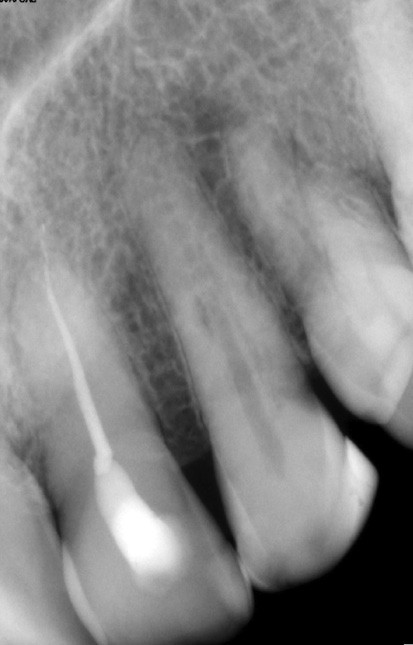

Si les isthmes sont particulièrement mis en évidence au niveau des molaires mandibulaires, cela devient médicalement important au niveau des molaires maxillaires.

La diffusion bactérienne et de leurs toxines, au niveau des molaires maxillaires est à l’origine d’un grand nombre de sinusites maxillaires chroniques, d’origine dentaire. Celles-ci sont principalement causées par l’absence de traitement du deuxième canal MV, qui existe dans 90 % des cas, et il est à noter que ces deux canaux – MV1 et MV2 – sont également reliés par un isthme.

Le nettoyage des isthmes intercanalaires reste un réel problème, et semble responsable de nombreux échecs [43]. Par ailleurs, il est nécessaire d’utiliser des instruments qui évitent de propulser les débris, tant apicalement que latéralement, en obturant les entrées isthmiques avec des débris compactés.

L’utilisation d’instruments en nickel titane, tels que le XP Shaper (FKG), le Vortex blue (Dentsply) ou le Profile (Dentsply), optimise la remontée des débris et s’inscrit dans cette nouvelle philosophie. En conséquence, la combinaison XP Shaper, XP Finisher et l’irrigation avec l’Er:YAG semblent optimiser nos traitements [44,45].